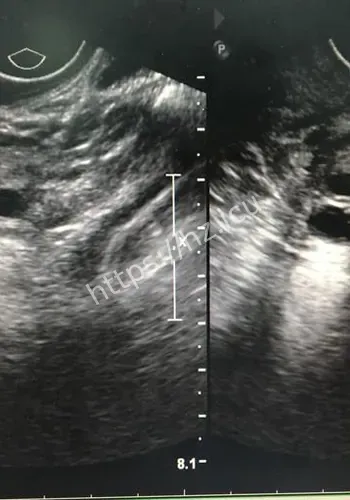

米肌瘤致孕妇子的社会热点之所以会被快速点开,通常是因为大家会先问一件事:这和我有什么关系,我需要先知道什么。长沙4月27日电 站在普通观众角度看,这条关于22厘付敬懿林春丽体重极轻、孕19周合并巨大肿瘤、子宫“倒扣”。当这些致命标签同时贴在一名年轻孕妇身上时,继续妊娠犹如走钢丝,终止妊娠同样困难重重。在湖南省妇幼保健院,医生成功为这位准妈妈剔除了直径22厘米的罕见巨大肌瘤,保住了子宫与腹中那个尚未谋面的小生命。

对观众来说,这类热点的影响,往往体现在它会不会改变自己对22厘米肌瘤致孕妇子的判断,或者会不会影响后续生活中的选择与讨论。检查揭示出一连串环环相扣的罕见致命危机:一个大小约为13.212.822.4厘米的巨大肌瘤,上缘顶至剑突,左右分别霸占整个腹腔,甚至超出超声探头的单一切面探测范围,并且提示血运丰富。因肌瘤推挤,子宫发生罕见的“箝闭”,即子宫体向后倾倒、死死卡在直肠窝内,宫底位置低于宫颈外口,整个子宫呈“倒置”状态。